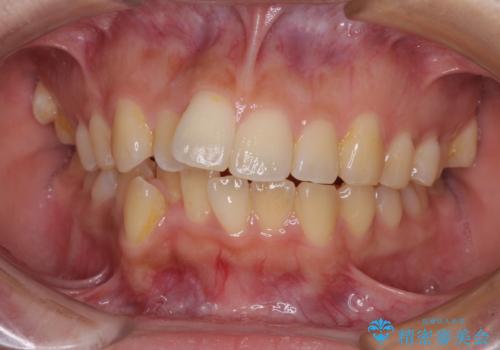

50代女性 八重歯を矯正治療 歯並びの中等度のがたつき